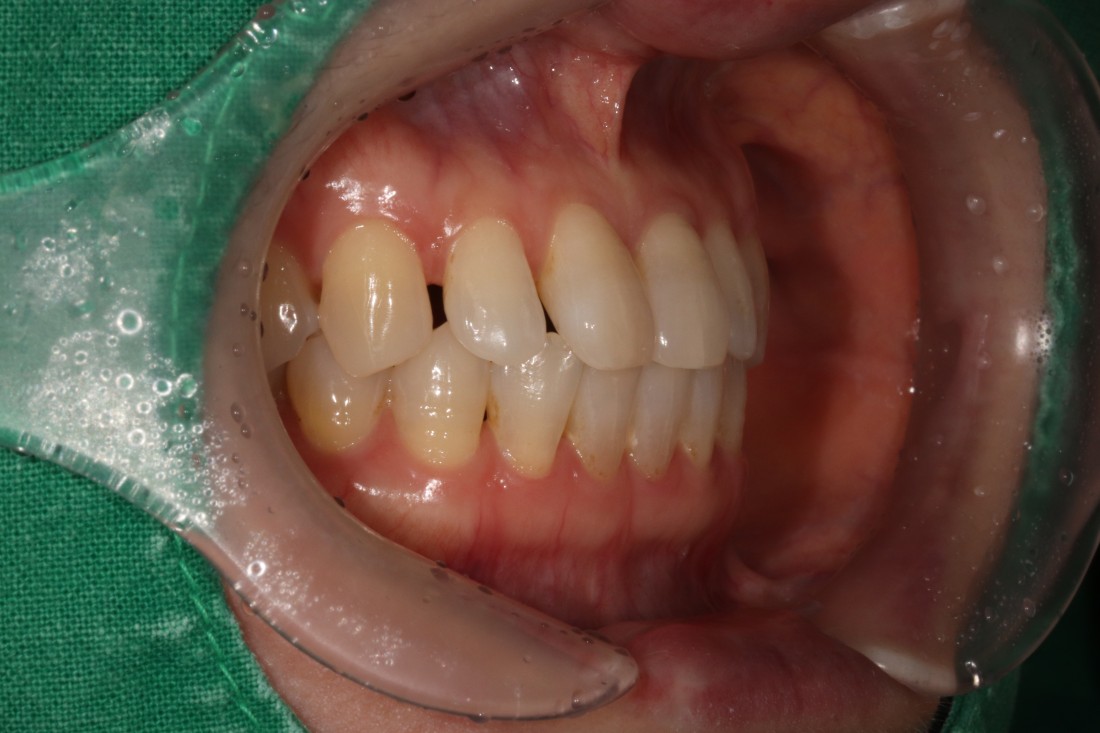

광주 무삭제 라미네이트 치과를 검색하면

정말 많은 치과가 나오는데요.

광고성 글이 아닌

진짜 라미네이트 진료 전/후 사진을

투명하게 공개하는 치과가

가장 신뢰할 수 있으실 겁니다.

광주 무삭제 라미네이트 진료는

경험이 풍부한 라미네이트 의료진이 있는

새로네이트 치과를 선택하세요!